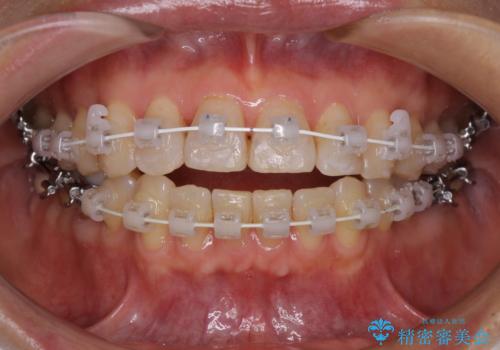

- 矯正装置

- 審美装置

- 前歯のデコボコを気にして来院された患者様です。

インビザラインでもワイヤー装置でも対応可能であったので、両者のデメリットをご説明し、選択していただくことになりました。

マウスピース矯正の装着時間の長さや自己管理の重要性を煩わしいと感じられ、低依存で確実に治療ができるワイヤー矯正を選択されました。

舌突出癖により、上下前歯がなかなか接触せずに治療期間を要しましたが、舌のトレーニングにより無事に治療を終えることができました。